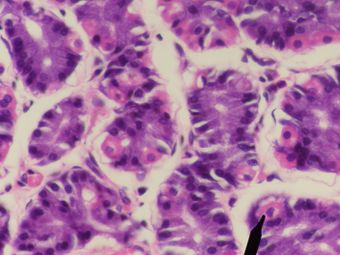

خلية جدارية (معدة)

خلايا جدارية بشرية (باللون الوردي) - المعدة. | |

الخلايا الجدارية وتُعرف أيضاً بالخلايا المفرزة للحمض oxyntic أو الخلايا محددة الشكل delomorphous cells)، هي خلايا طلائية تُفرز حمض الهيدروكلوريك والعامل الداخلي. تقع هذه الخلايا في الغدد المعدية الموجودة في بطانة قاع وجسم المعدة.[1] تحتوي الخلايا الجدارية على شبكة إفرازية واسعة (القنيوات) والتي يُفرز من خلالها حمض الهيدروكلوريك عن طريق النقل النشط داخل المعدة. تتميز الخلايا الجدارية بوجود انزيم أتپيز الهيدروجين پوتاسيوم (H+/K+ ATPase) الذي ينقل أيونات الهيدروجين بعجس تدريج التركيز بحوالي 3-1 مليون، وهو أكثر ميل أيوني انحدارًا في جسم الإنسان. الخلايا الجداريّة تُنظَّم أولاً عن طريق هستامين، واستيل كولين، وگاسترين بإشارة من كلا المضامين المركزية والموضعية (انظر التنظيم).